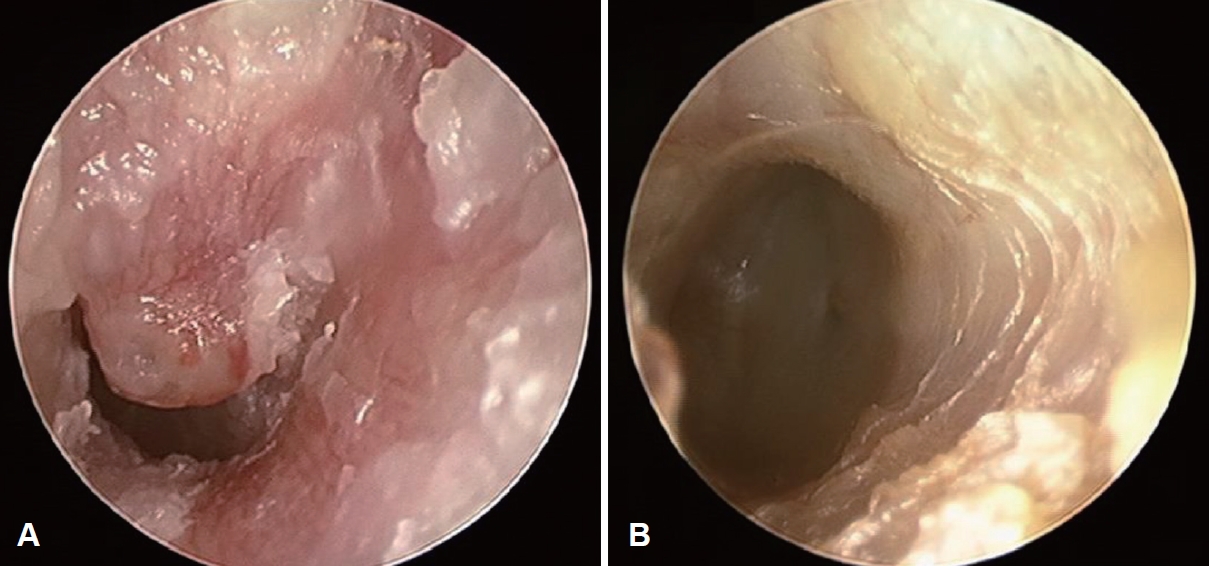

CaseThe subject of this case, a 78-year-old female patient with a history of hypertension, cholecystectomy visited the outpatient department with the main complaint of hearing loss on the left side that started 6 months ago. She did not complain of otalgia. Otoscopic examination revealed a reddish round mass originating from the anterior and superior walls of the EAC, causing nearly complete occlusion (Fig. 1A). Pure tone audiometry performed at the initial outpatient visit showed moderate to severe mixed hearing loss on the left side (Fig. 2A).

After surgery, the neo-TM and EAC returned to normal, with pure tone audiometry showing a reduction in the air-bone gap (Figs. 1B and 2B). Unfortunately, the myxoma lesion reappeared 6 months after the surgery during the follow-up. As the patient did not want to be re-operated considering her old age, she is currently being managed with a monthly marsupialization in the outpatient clinic. As conductive hearing loss was the only symptom caused by the myxoma, regular marsupialization of the mucoid contents of the tumor could effectively alleviate the patient’s complaint.

NotesAuthor Contribution Conceptualization: Jung Mee Park. Data curation: Jun Seop Kim, Sukjune Byun, Chang Heum Han. Formal analysis: Jung Mee Park. Investigation: all authors. Project administration: Jung Mee Park. Resources: Jung Mee Park. Supervision: Jung Mee Park. Visualization: Jun Seop Kim. Writing—original draft: Jun Seop Kim, Jung Mee Park. Writing—review & editing: all authors. Fig. 1.Otoscopic images of the lesion. A: Pre-operative otoscopic image shows a reddish, round mass occluding the left external auditory canal (EAC). B: Post-operative otoscopic image at 6 months shows a clear neotympanic membrane and EAC. Fig. 2.Pure-tone audiometry of the patient. A: Pre-operative pure tone audiometry shows a moderate to severe mixed hearing loss on the left side. B: Post-operative pure tone audiometry shows a reduced air-bone gap. Fig. 3.Radiological images of the lesion. A: Temporal bone CT. Soft tissue lesion in the left external auditory canal (EAC) with tympanic membrane (TM) thickening (red arrow) but without any bone lysis. B: Temporal bone MRI. 8 mm non-enhancing T2-weighted image hyperintense mass at left medial EAC, abutting to TM (yellow arrow). Fig. 4.Pathological images of the lesion. A: Pathologic evaluation reveals a well-circumscribed mass with predominantly myxoid stroma and partly fibrocystic change (hematoxylin and eosin [H&E], ×10). B: Bland stellate- or spindle-shaped cells are scattered in the hypovascular myxoid matrix (H&E, ×100). C: Some muciphages are intermingled with thin strands of vessels (H&E, ×400). Table 1.Differentiating diagnostic features of various EAC tumors Table 2.Image features among EAC cholesteatoma and myxoma REFERENCES1. Andrews T, Kountakis SE, Maillard AA. Myxomas of the head and neck. Am J Otolaryngol 2000;21(3):184-9.